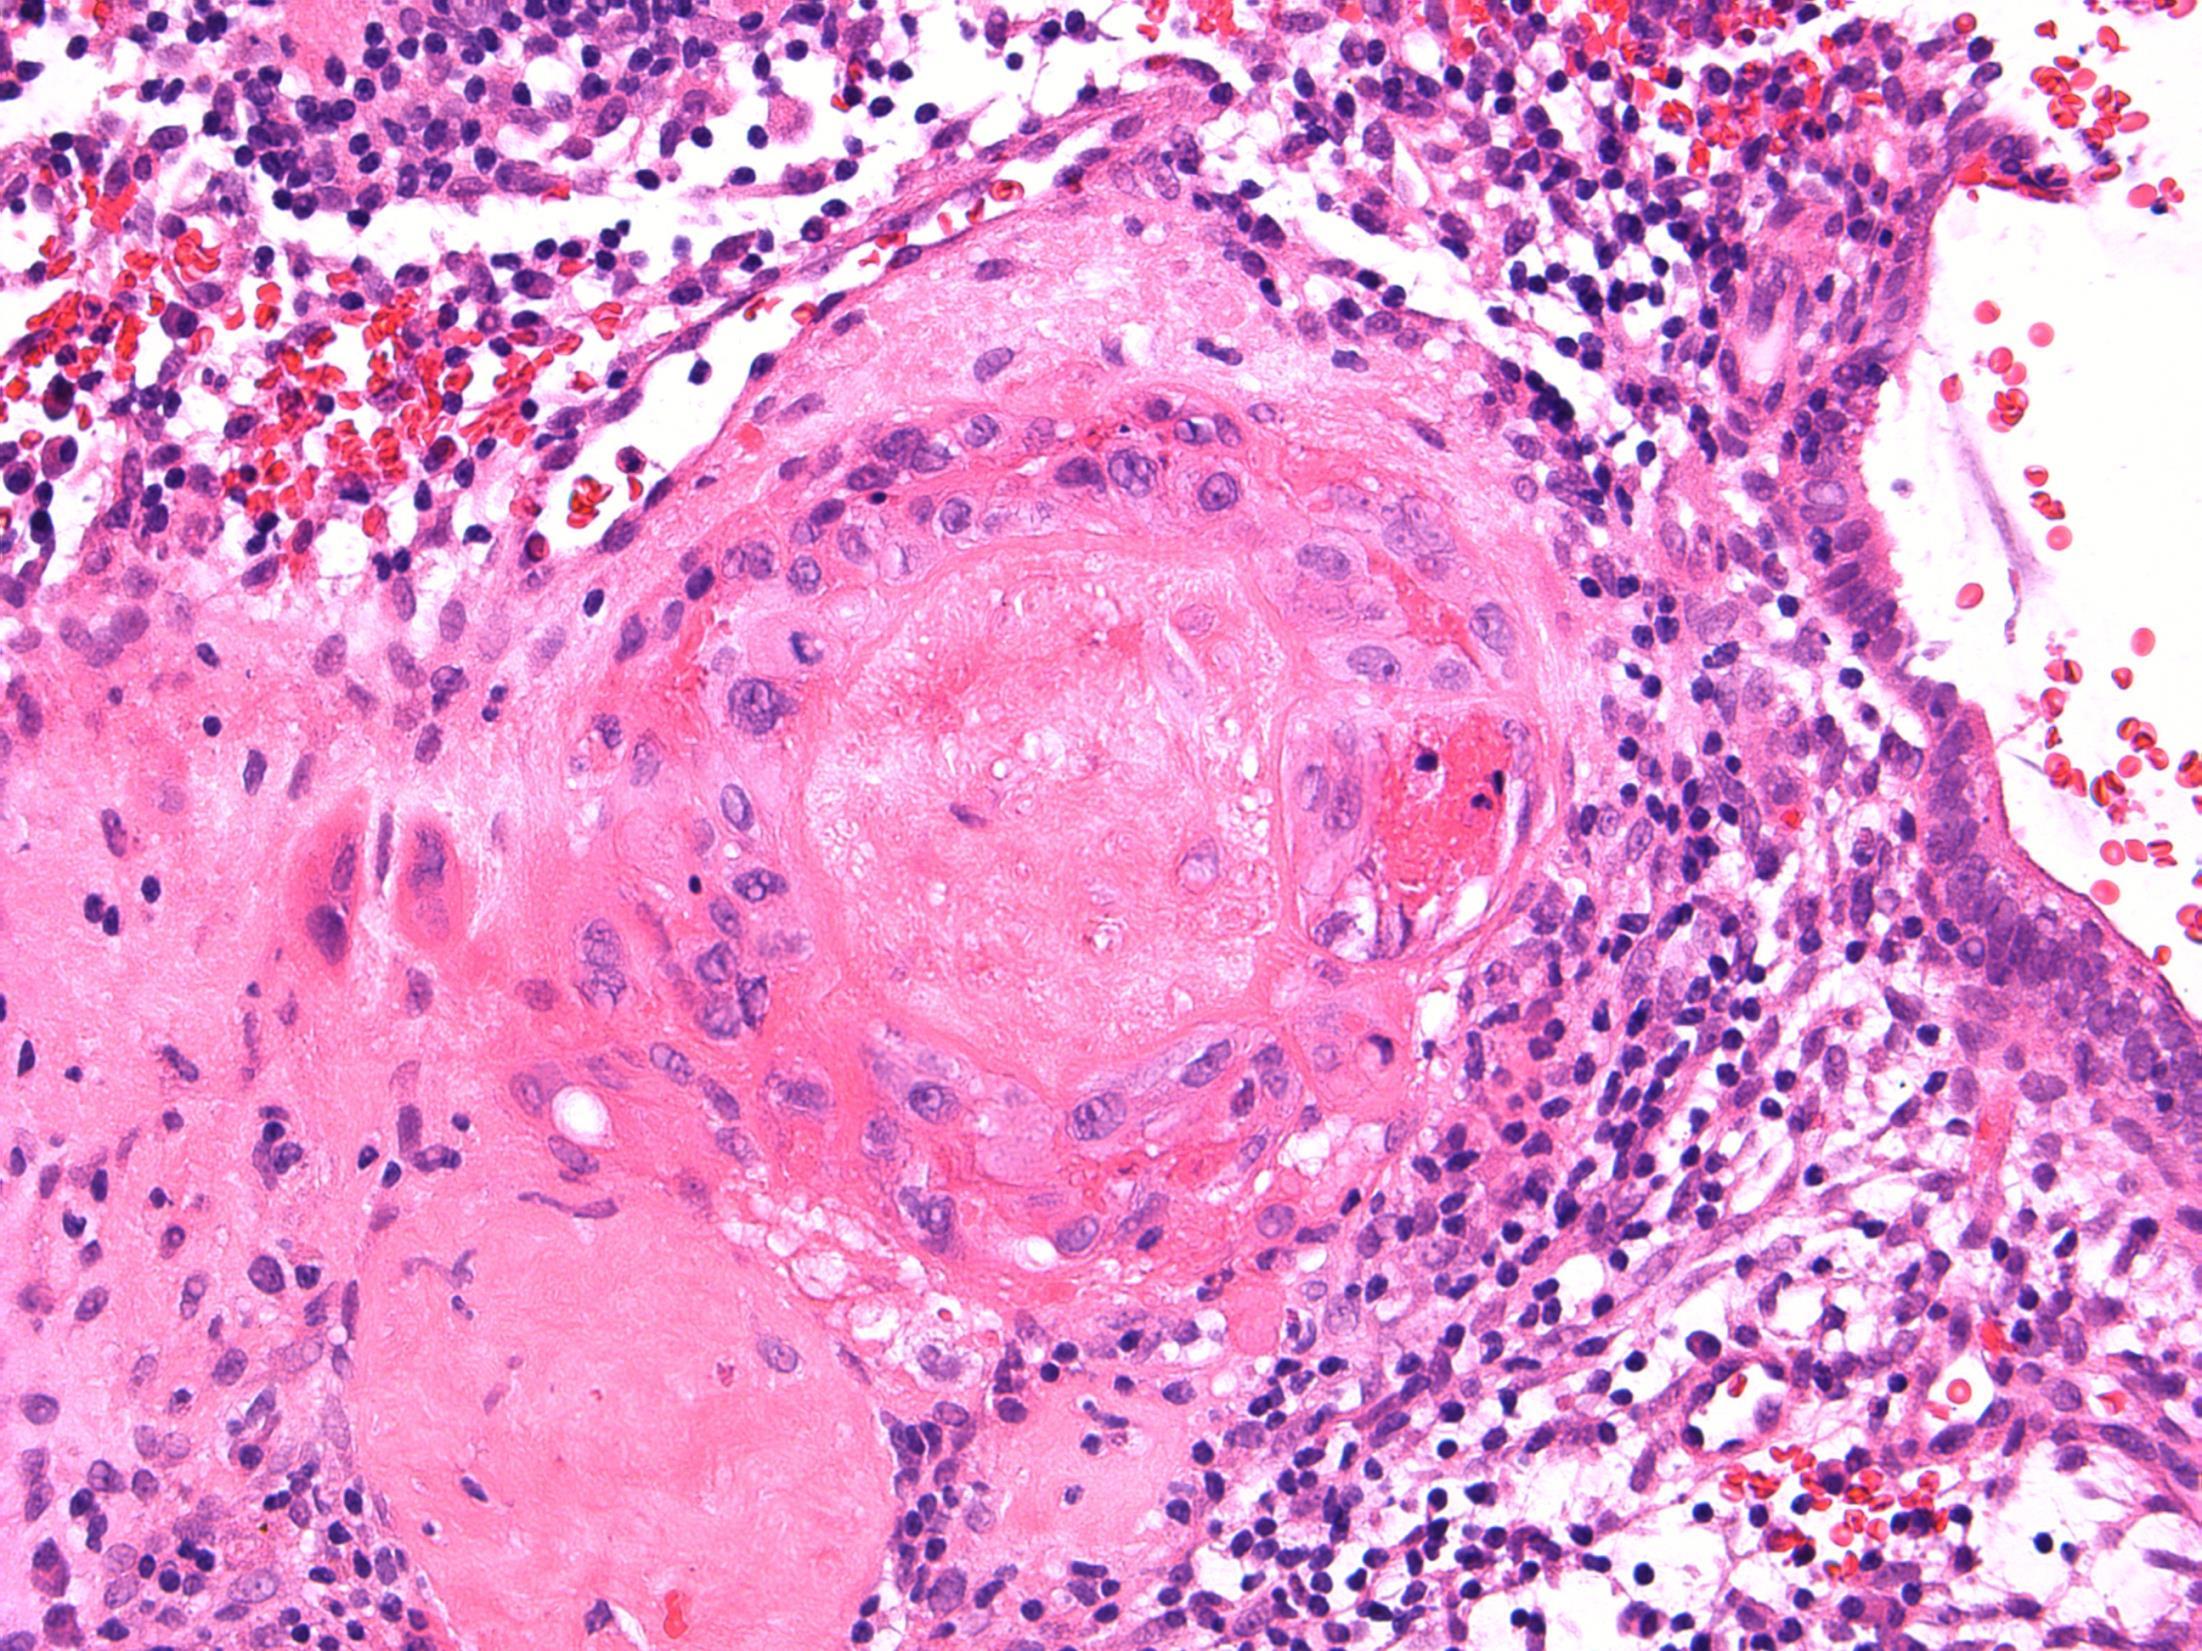

Verrucous carcinoma

Description: Abrupt transition between tumour and epithelium. Plump papillary invaginations of thickened and infolding epithelium, hyperkeratosis. Lack of cytological atypia, suprabasal mitoses. Retraction of normal epithelium at margin. Diagnosis: Verrucous carcinoma Differential Diagnosis:

Conventional SCC – cellular atypia • Squamous papilloma – more exophtyic & branching, less keratin • Reactive inflammatory epithelial hyperplasia – most difficult but rete pegs more slender and anastomosing; no mitoses; macro correlation Plan: Correlate with previous biopsies ( often quite bland so can be inconlusive) Examine further blocks for worse areas and measure margins. Comments: In head and neck – oral cavity and larynx Often large, locally aggressive, pushing margin Better prognosis than SCC